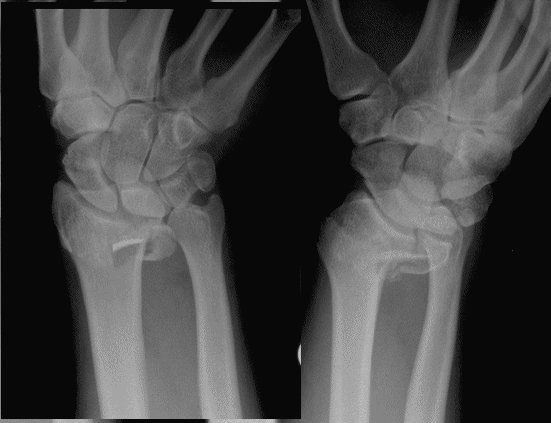

Case 4 Preop

Case 4 CT